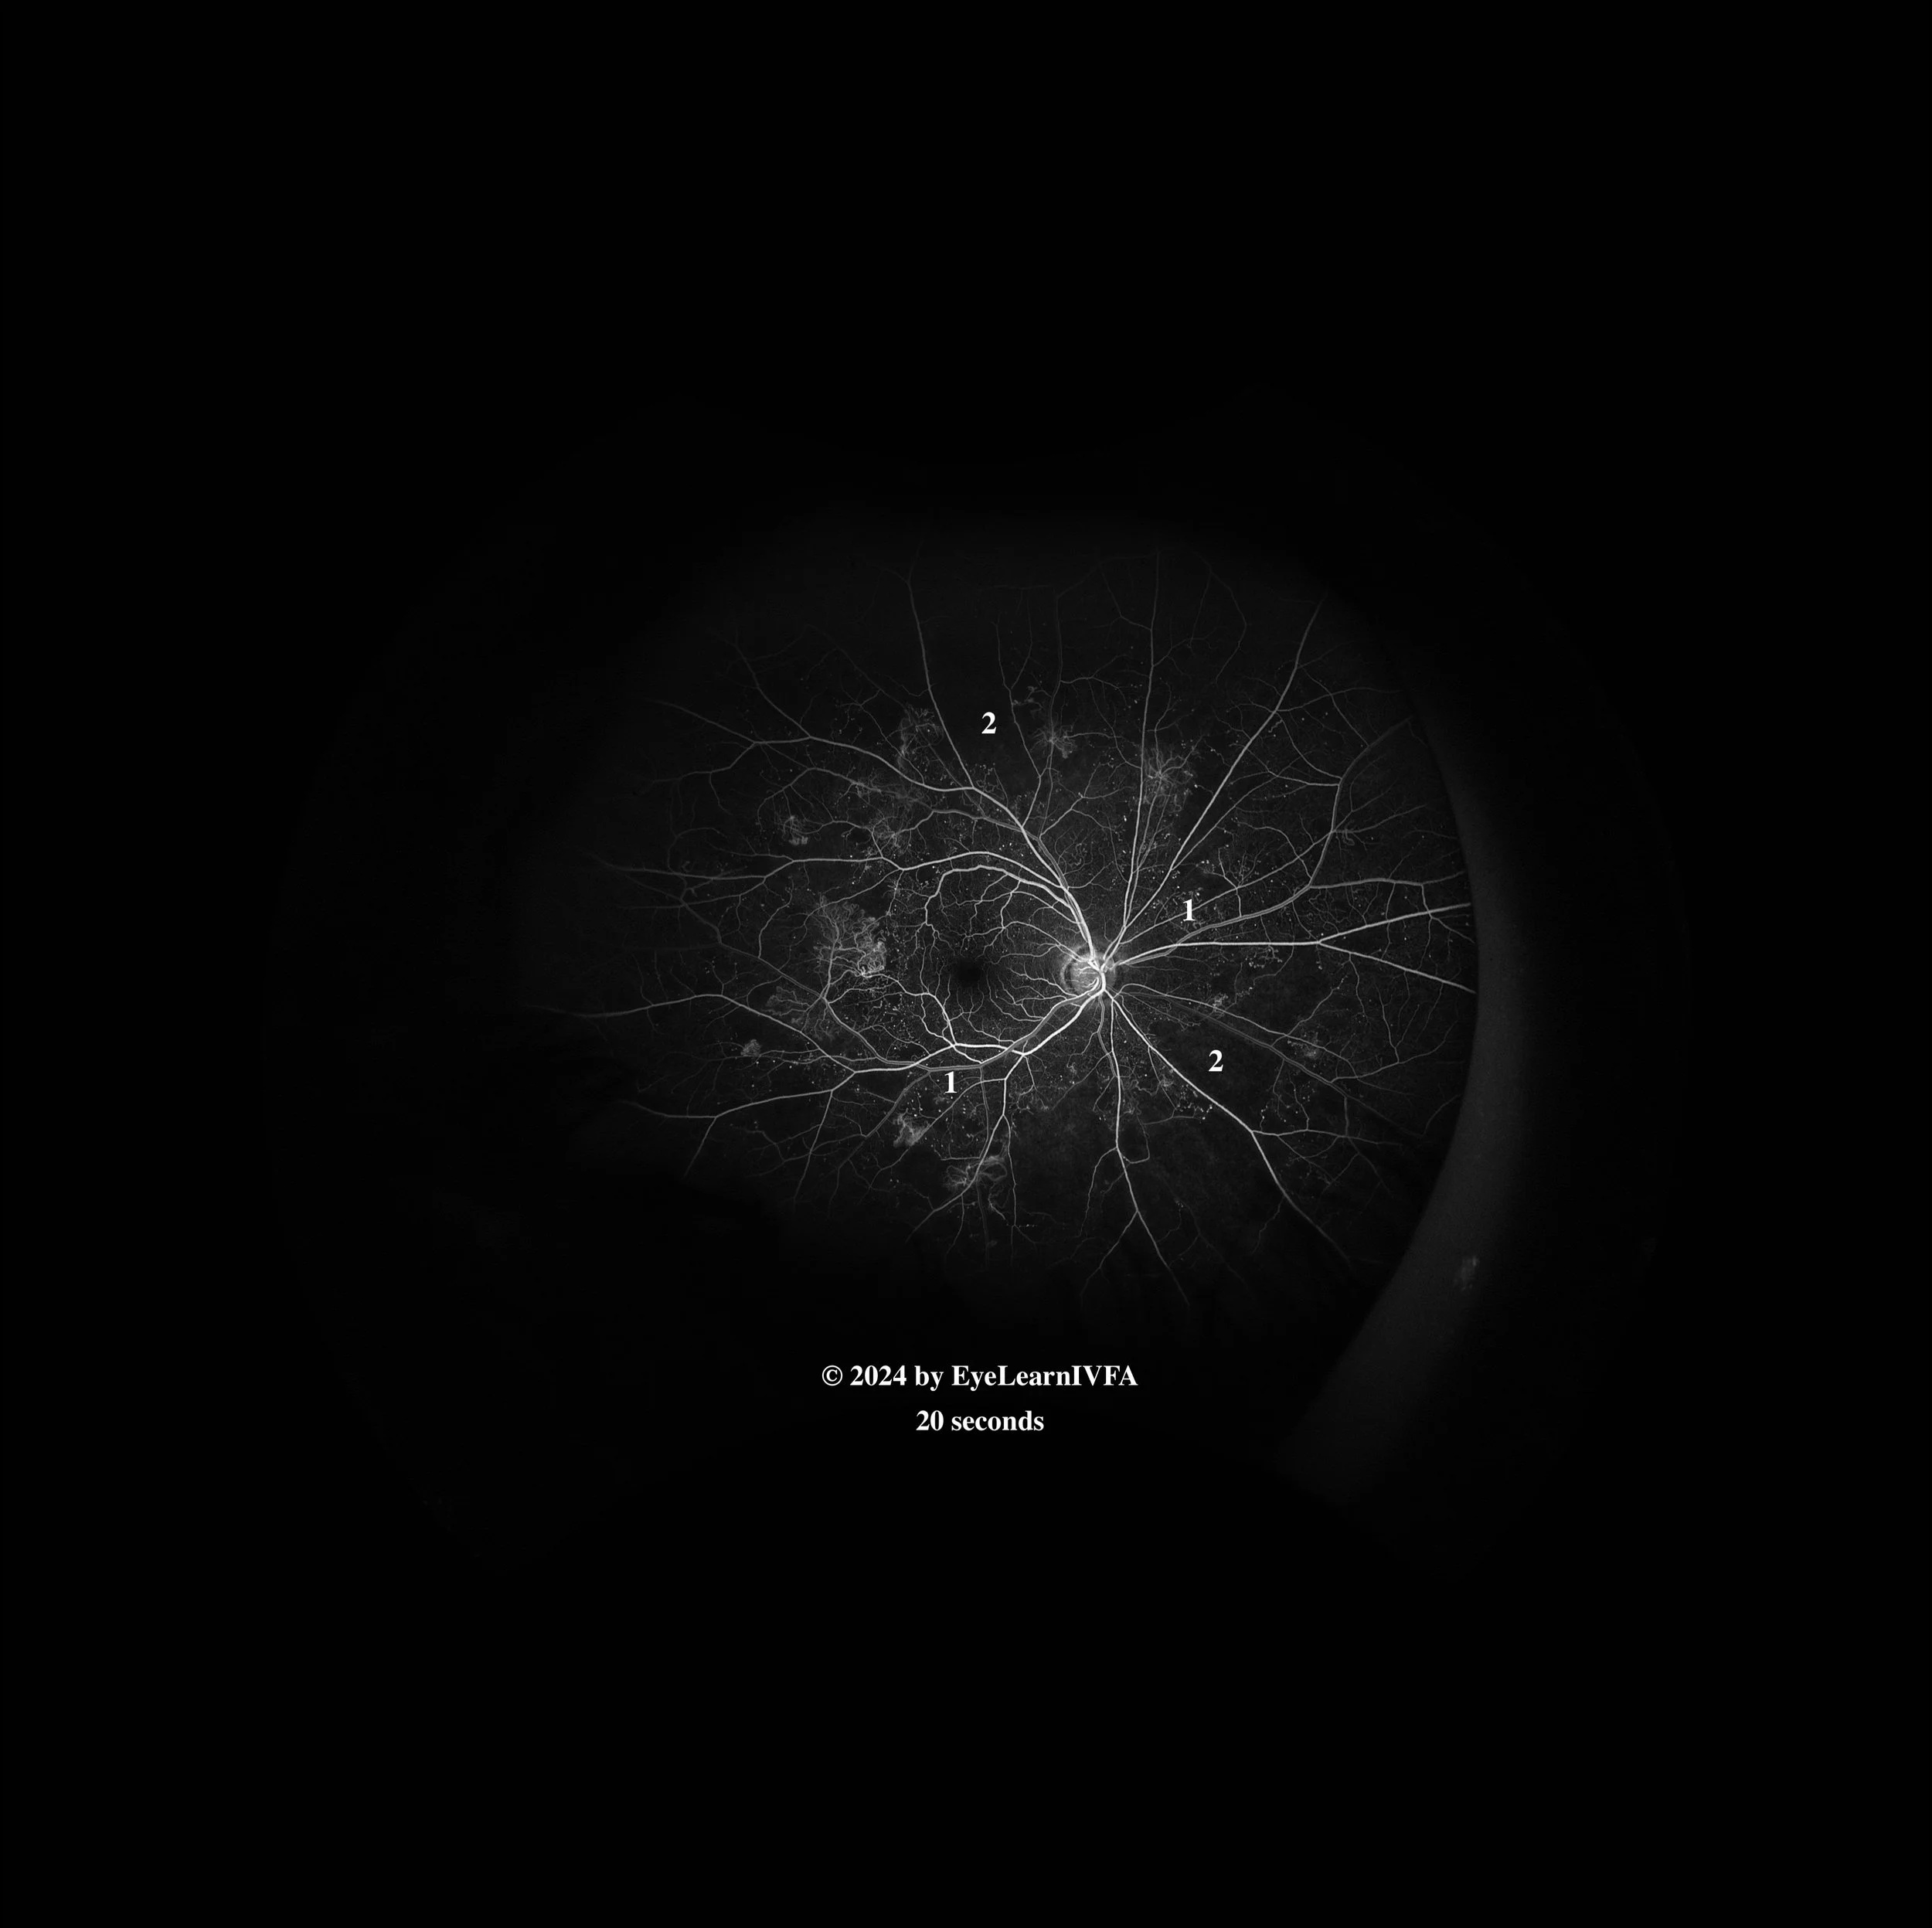

• IVFA at 20 seconds

Early arteriovenous phase with laminar flow.

Key features include:

• Persistent focal spots of hyperfluorescence secondary to microaneurysms (1).

• Faint areas of hyperfluorescence with irregular borders at the edges of the posterior pole secondary to neovascularization elsewhere (NVE). (1)

• Hypofluorescence in the supra-temporal region and inferonasal region from non-perfusion secondary to capillary drop-out (2).